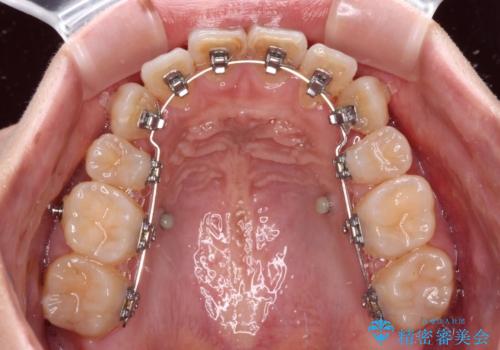

気になる八重歯を目立たない装置で改善 ハーフリンガル矯正

- ハーフリンガル

- 八重歯や前歯のデコボコを気にして来院された患者様です。

目立たない装置を希望されたので、上顎が裏側装置のハーフリンガルを選択し、上下左右の小臼歯(計4歯)を抜歯して矯正治療を行うこととしました。

補助装置を併用することで、八重歯を速やかに改善し、治療期間の短縮を図ることとしました。